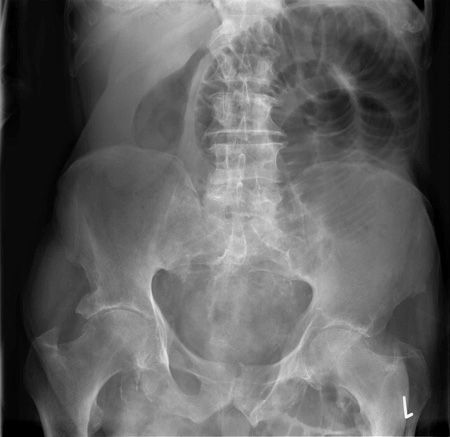

X-RAY QUIZ: Which finding is present on this image?

A: Normal X-ray image

B: Sail sign

C: Meniscus sign

D: Pneumothorax

E: Air bronchogram

Start Quiz bit.ly/36i1txn